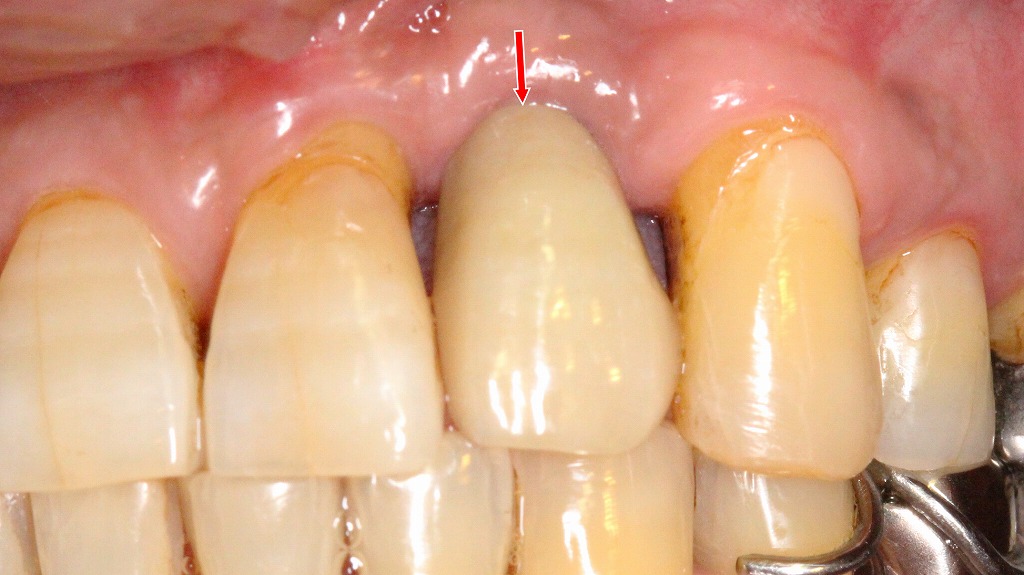

左上2番欠損に対するインプラント治療の経過:欠損から最終補綴装着まで

左上2番欠損に対し、従来のブリッジ治療のように両隣在歯を大きく削る必要がないことから、インプラント治療を選択しました。適切なポジションでインプラントを埋入し、ジルコニアセラミックの上部構造を装着することで、周囲歯を守りながら自然な審美性と咬合機能を回復しています。ブリッジと比べ、隣在歯への負担軽減・清掃性・長期的安定性などで有利となる治療方法であることが、治療結果からも確認できます。